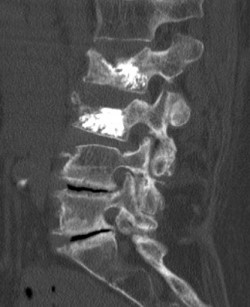

Abbildung 2: Das Bild zeigt die Aufrichtung und Zementauffüllung des betroffenen Wirbelkörpers (Kyphoplastie).

Da Wirbelkörperbrüche beim älteren Menschen häufig auch ohne Unfall auftreten können (pathologische Frakturen), liegt unser klinischer Fokus neben der optimalen chirurgischen Therapie auf der Behandlung der zugrunde liegenden Osteoporose, um weiteren Knochenbrüchen vorzubeugen.

Wirbelkörperbrüche sind oft mit starken Rückenschmerzen verbunden. Wenn es trotz Schmerztherapie zu keiner Linderung kommt, ist eine Kyphoplastie, die Aufrichtung und Zementauffüllung des betroffenen Wirbelkörpers, sinnvoll (Abb.). Dieser Eingriff kann über zwei 1 cm lange Hautschnitte erfolgen. Auch hier erlaubt das routinemäßig computergestützte Planungssystem höchste Präzision.